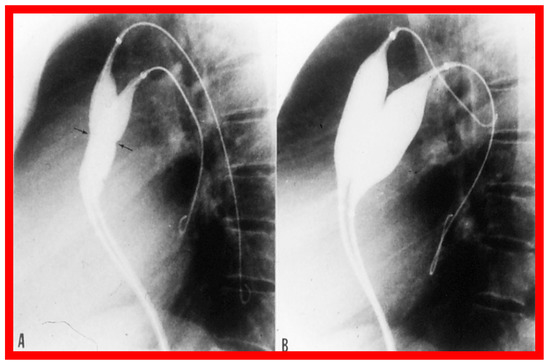

3.4. Aortic Coarctation, Postsurgical

4.4. Aortic Coarctation, Postsurgical

5.4. Aortic Coarctation, Postsurgical

6. Long-Term Results